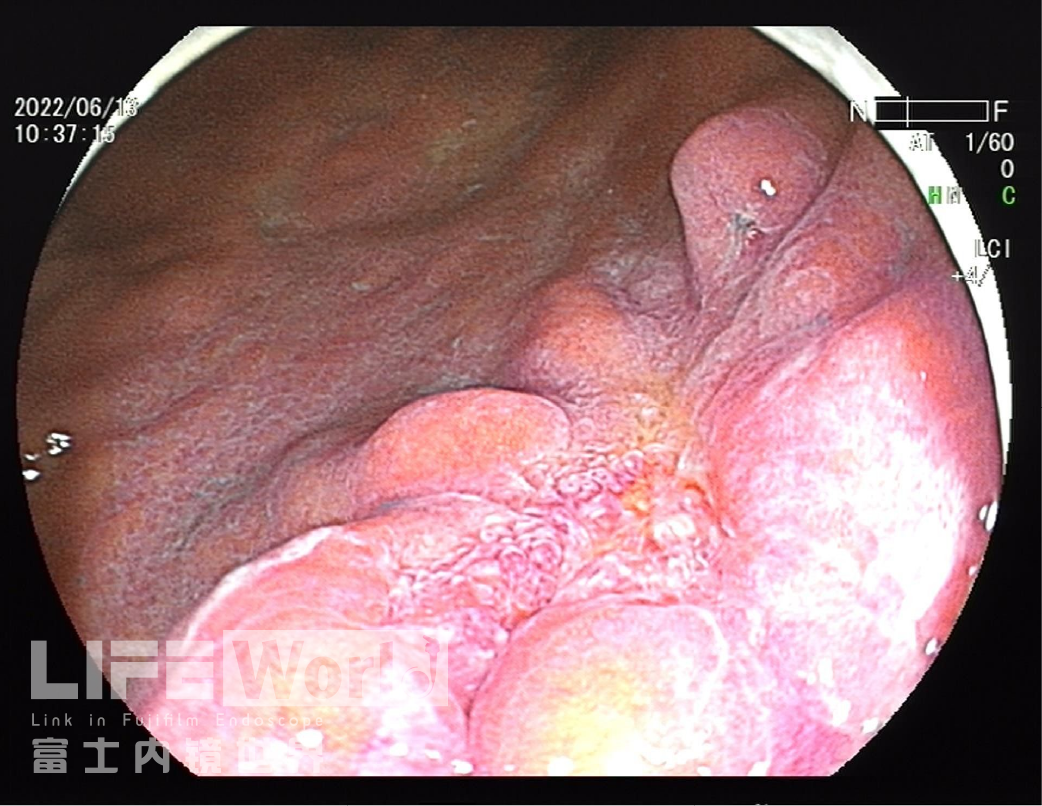

白光观察:胃体下段大弯侧可见一处中央凹陷的病变,色红,范围约1.2×0.6cm,周围黏膜集中、中断。

LCI模式:病变为橙黄色,周围黏膜呈紫红色。

白光+LCI+BLI的对比观察。